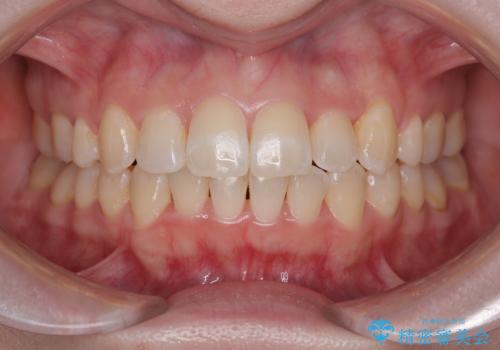

- 「前歯のねじれを改善したい」とのご希望で当院に来院された患者様です。

診察の結果、上下の前歯部に**叢生(そうせい/歯のガタガタ・重なり)**が認められました。

特に上の前歯にはねじれや重なりがあり、審美的にも清掃性にも影響している状態でした。

また、上顎前歯の重なっていた部分にはむし歯が見つかり、治療中に適切な処置を行っています。

矯正治療期間はわずか10か月と、比較的短期間で終了しました。

前歯のデコボコがなくなり、見た目の印象が大きく変わっただけでなく、歯磨きがしやすくなり、むし歯や歯周病のリスクが大きく減少しました。